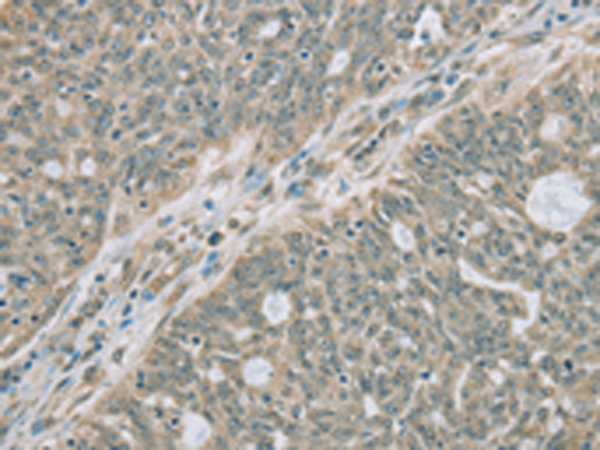

分类: 科研抗体货号: P08286别名: PCPH; CD39L4; NTPDase-5应用: WB,IHC反应种属: Human, Mouse, Rat